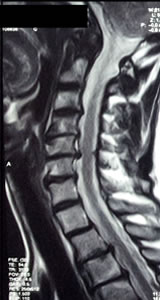

- Resonancia Magnética de la columna vertebral es el mejor método de imágenes de la médula espinal y las raices

nerviosas, los discos intervertebrales y los ligamentos.